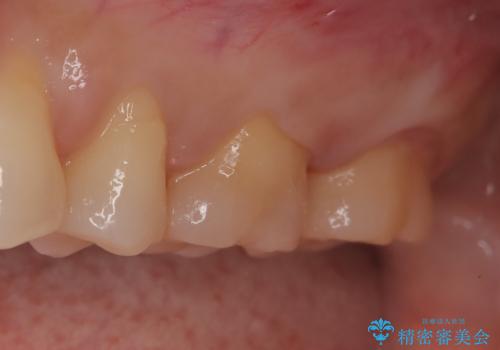

【メタルフリー】セラミックインレーの修復

- メタルフリーを希望された患者さんです。

金属を除去し虫歯の処置をしたあとセラミックインレーにて修復しました。